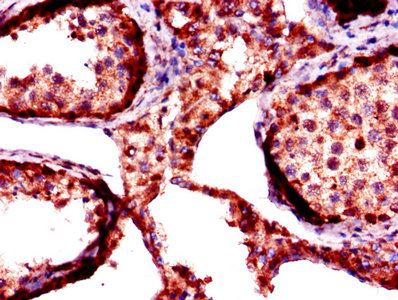

Immunohistochemistry of paraffin-embedded human testis tissue using CSB-PA008702LA01HU at dilution of 1:100

Immunofluorescent analysis of MCF-7 cells using CSB-PA008702LA01HU at dilution of 1:100 and Alexa Fluor 488-congugated AffiniPure Goat Anti-Rabbit IgG(H+L)